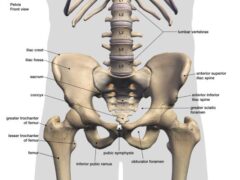

歩くという動作は、

腰・骨盤・股関節・膝・足首が連動して初めて成立します。

そのため、どこか一か所の動きが悪くなると、

別の場所が無理に働き、結果として痛みが出てしまいます。

■ 腰や骨盤の動きが硬いと、股関節に負担が集まる

本来、歩行中は

骨盤がわずかに前後・左右に動くことで、

股関節への衝撃やねじれが分散されます。